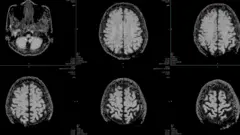

A principal teoria entre os cientistas que estudam o papel do cérebro na enxaqueca é que o ataque é uma onda elétrica lenta e anormal, que se espalha através do córtex cerebral, conhecida como depressão cortical alastrante (CSD, na sigla em inglês).

Em março de 2025, cientistas capturaram a onda em tempo real, enquanto monitoravam o cérebro de uma paciente de 32 anos, sendo preparada para cirurgia. Eles captaram a onda através de 95 eletrodos inseridos no seu crânio.

Ela se espalhou a partir do seu córtex visual, o que explica por que algumas pessoas apresentam sensibilidade à luz e visões de auras, segundo Moskowitz. Dali, ela atravessou todo o cérebro por mais 80 minutos.

A variação da natureza da onda ajuda a explicar por que algumas pessoas veem apenas uma aura, outras veem uma aura antes da dor de cabeça e há um grupo que tem dor de cabeça antes da aura, segundo Moskowitz. Tudo depende dos padrões da onda.

Mas a depressão cortical alastrante também explica outros sintomas neurológicos que surgem durante um ataque de enxaqueca, como a fadiga, bocejos, nevoeiro cerebral e vontade de comer alimentos específicos.